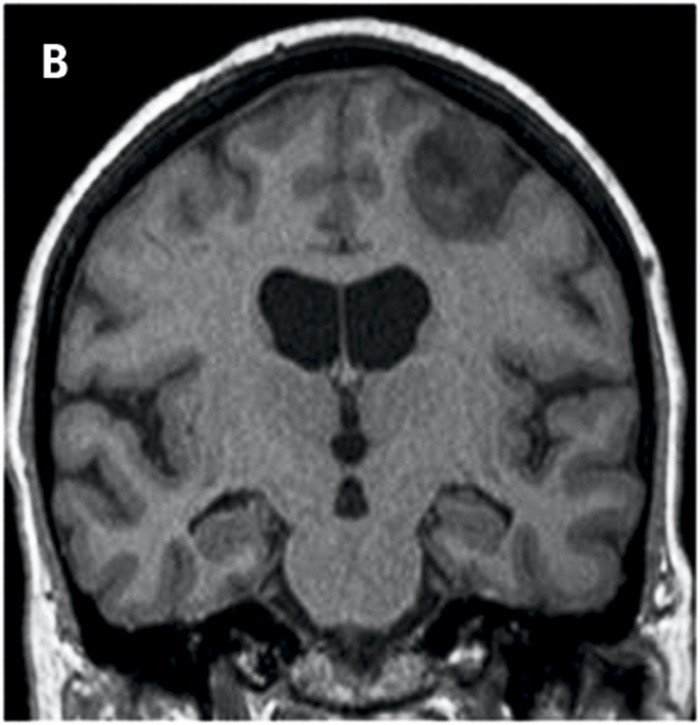

Bedömningen sker enligt en femgradig skala, 0–4, där MTA 0 och MTA 1 visar normala förhållanden och MTA 2–4 ökande grad av atrofi. MTA 2 är patologiskt hos patienter yngre än 70 år och MTA 3 är patologiskt hos alla patienter under 80 år, medan MTA 4 alltid måste uppfattas som patologiskt oavsett patientens ålder (Figur 1) [15].

Metoden togs ursprungligen fram för bedömning av MR-bilder men kan även användas för bedömning av medial temporallobsatrofi med dagens DT-teknik och för jämförelse mellan MRT och DT [16] (Figur 2). Resultat från denna metod har visats vara signifikant korrelerade med manuella mätningar av hippocampus [15], och sensitiviteten och specificiteten är jämförbara med automatiska metoder för volymberäkningar och mätning av kortikal tjocklek [17]. När det gäller reliabilitet (intra- och inter-) över tid är den mycket hög för en erfaren bedömare. Dock är reliabiliteten något lägre mellan två bedömare om de inte arbetar tillsammans. Den är också starkt beroende av erfarenhet hos bedömaren [18].

Figur 1. MTA-graderna 0 (A), 1 (B), 2 (C), 3 (D) och 4 (E).

Figur 2. MR från år 2009 (A) och DT från år 2012 (B) på samma patient med diagnosen Alzheimers sjukdom. Notera progress av såväl medial temporallobsatrofi som ventrikeldilatation.